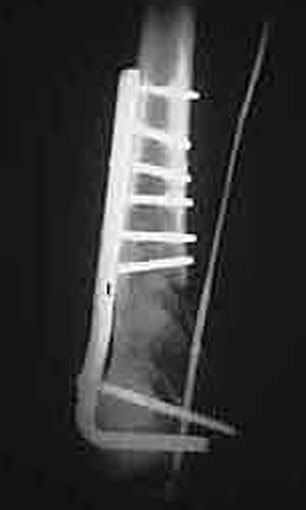

An initial injury film shows a closed supracondylar femur fracture with an arteriogram done for questionable signs of arterial injury showing a nonocclusive intimal flap of the popliteal artery. Since this arterial injury fit the published criteria for nonop observation, our orthopedic surgeons went ahead and did ORIF. 6 weeks later a F/U angio shows complete resolution of the intimal flap -- unnecessary surgery thus avoided.

6 weeks later

I'll try--there is an intraluminal defect consistent with a flap.

Click to zoom in on these images: